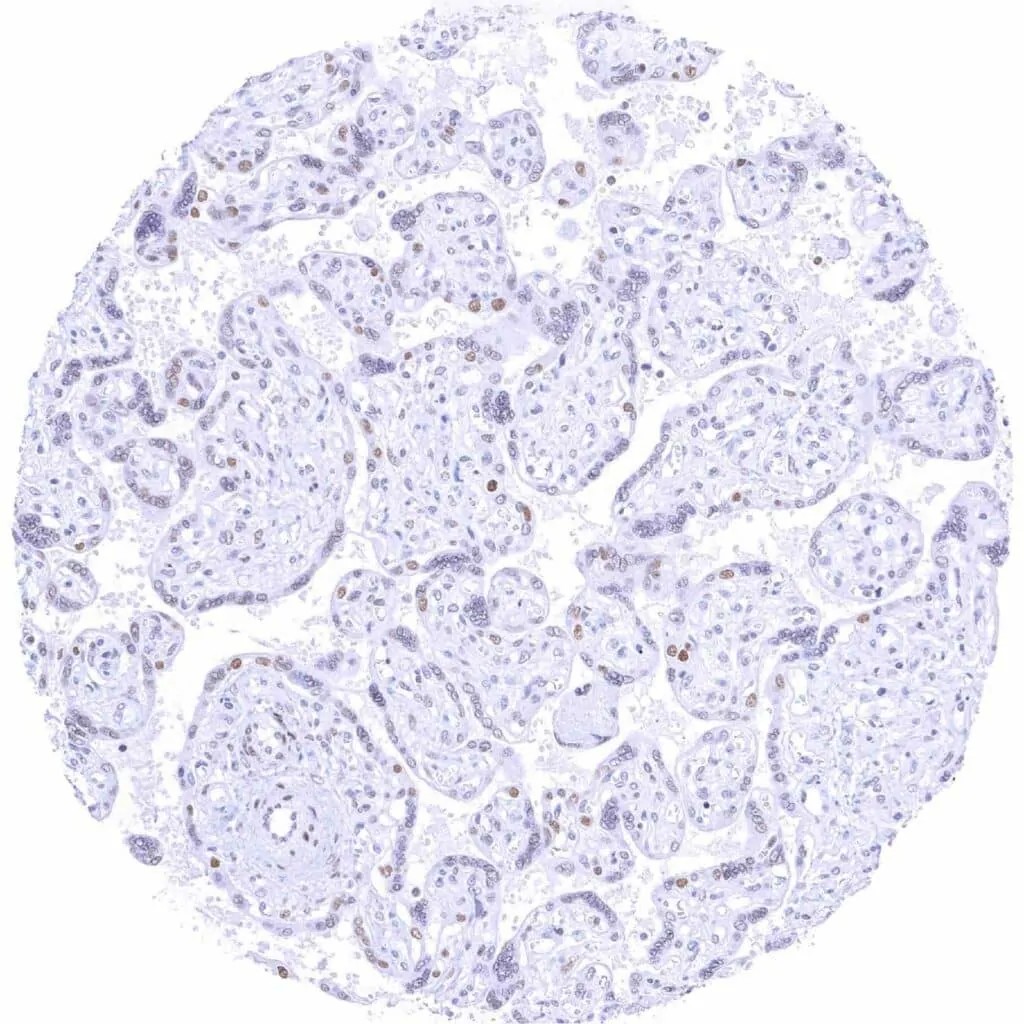

Placenta, early – Moderate to strong TLE1 staining of trophoblast and some stroma cells